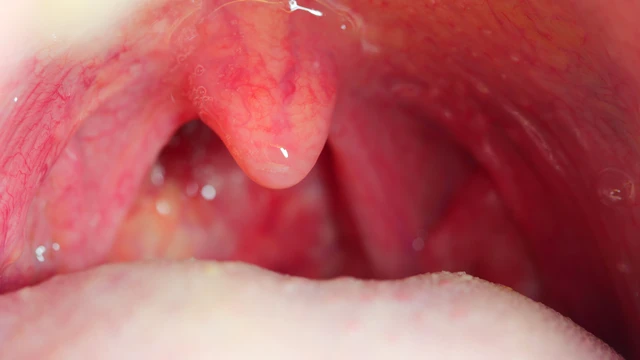

Hậu quả sau khi cắt amidan là vấn đề được nhiều người quan tâm trước khi quyết định phẫu thuật. Mặc dù đây là thủ thuật khá phổ biến và an toàn, nhưng sau cắt amidan vẫn có thể xuất hiện một số ảnh hưởng như đau họng, chảy máu hoặc khó nuốt trong thời gian hồi phục.